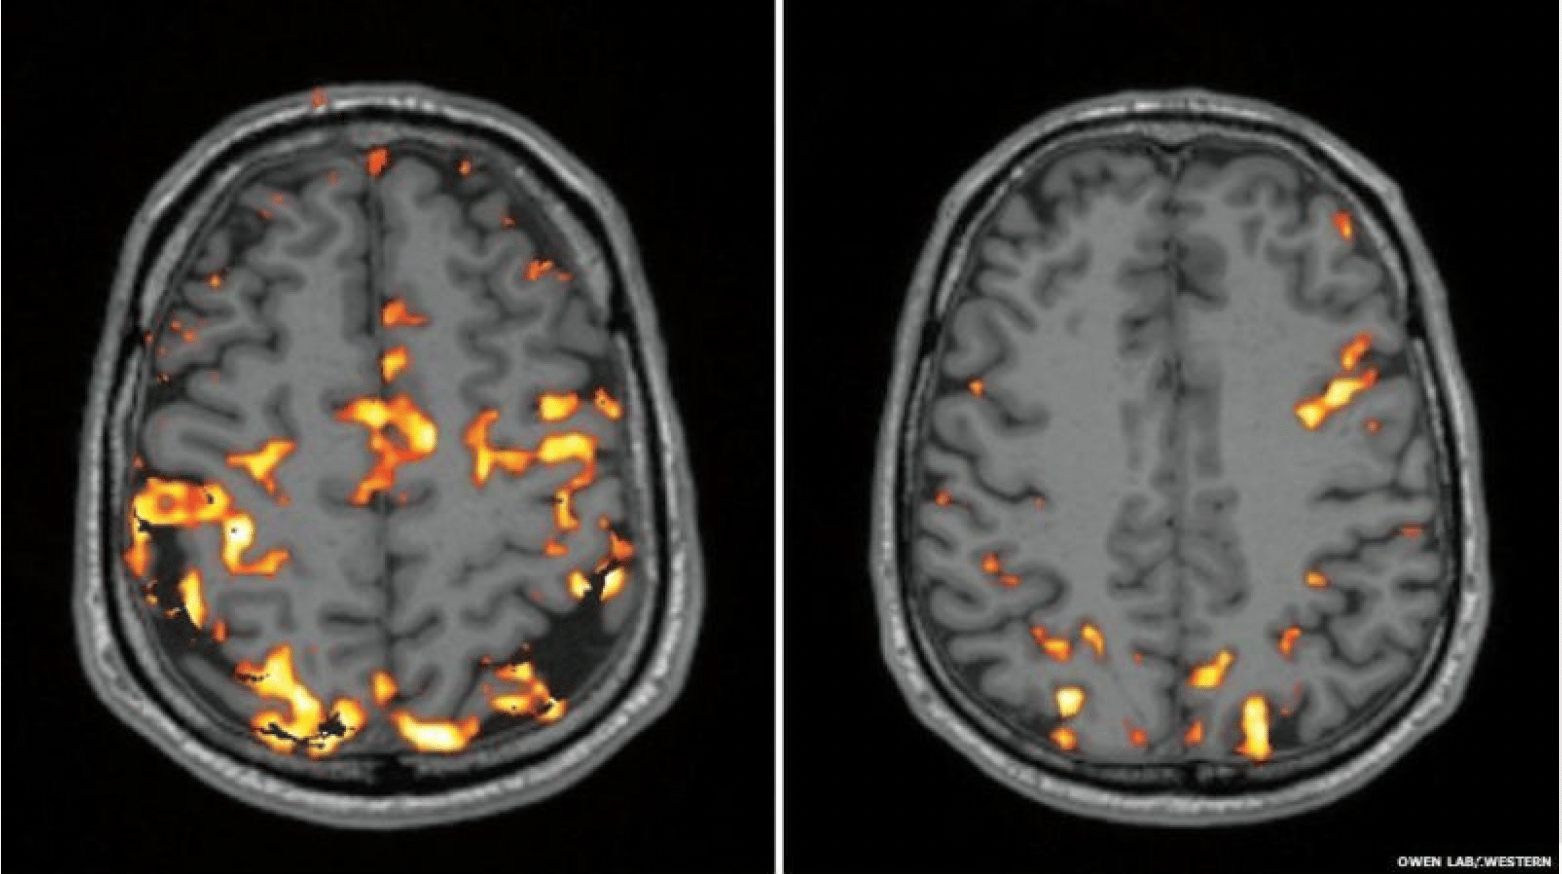

Nina mentions a striking visual comparison between two different brains: One belongs to a person who has had sufficient, high-quality sleep. The other belongs to someone sleep-deprived.

'Both brains are challenged with tasks requiring focus, concentration, memory, and creativity. You can see that the well-rested brain is vibrant and colorful, with strong connections between different brain regions, while the sleep-deprived brain is almost completely dimmed. If the necessary brain areas aren’t even ‘on,’ how are they supposed to communicate and function properly?'

'So, it’s a misconception to think you can just work four to five extra hours, pushing from 7–8 AM until 10–11 PM or even into the middle of the night. When it comes to financial decision-making, creativity, and organization, a lack of sleep creates a serious deficit for you.'